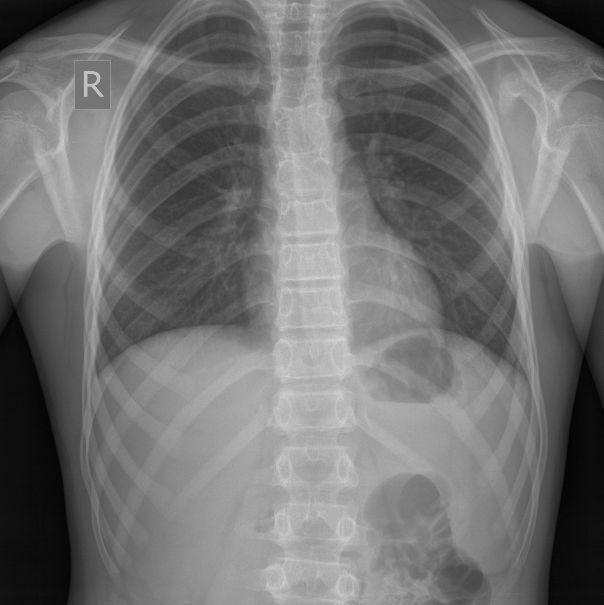

12-years old boy with torax palpable mass

12-years old boy with torax palpable mass 5x3 cm.

После УЗИ - сделал рентген, изменения в ребре есть, но в глаза не бросаются

Diagnosis of Ewing's Sarcoma is suspected